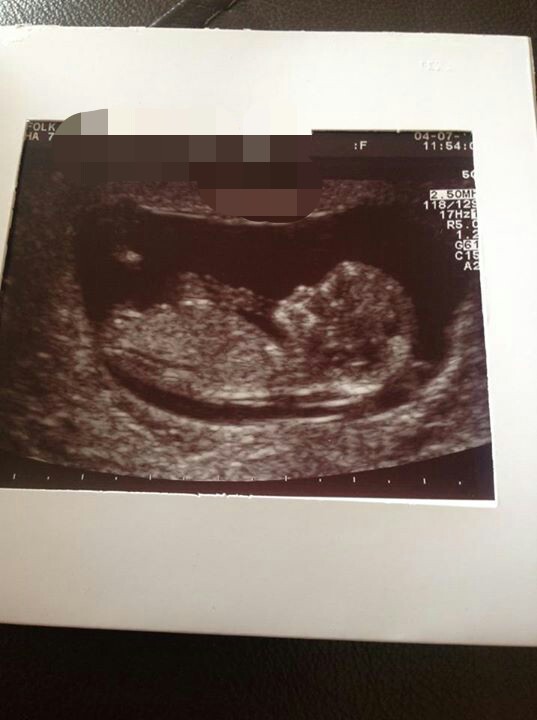

Hi lovely ladies, I'm posting for a friend she just had her scan tday and is nearly 12wks according to her scan tho she is convinced she's further along going by her period! What do you think?

There looks to be a shadow on top of that flat nub so I'm going 50/50 as not really clear enough to tell.

mm not sure on gender baby looks 12 weeks maybe 13.